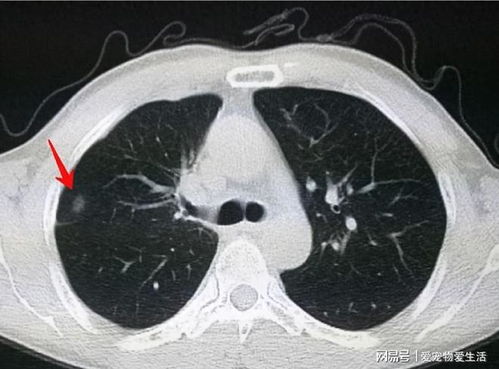

胸片诊断的精髓在于对微小病变的捕捉。即使是再资深的医生,面对模糊不清、充满噪点的影像,也可能“望洋兴叹”。“100%胸片曝光软件官方版”通过其卓越的细节锐化与降噪技术,帮⭐助医生将目光聚焦在那些肉眼难以察觉的细微之处。

高精度边缘检测与锐化:软件能够精准识别图像中的边缘信息,并对其进行局部锐化处理,使得肺纹理、支气管结构、肋骨边缘等重要解剖标志更加清晰可见。这对于识别早期肺结节、微小病变等至关重要。智能降噪算法:X射线成像过程中产生的噪点是影响图像质量的重要因素。

软件采用了先进的非局部均值滤波(NL-means)等算法,能够有效去除图像中的随机噪点,同时最大程度地保留图像的细节和边缘信息,避免出现“涂抹感”。纹理分析增强:针对肺部组织的纹理特征,软件还具备特殊的增强处理能力。它能够凸显肺实质的细腻纹理,帮助医生更好地评估肺气肿、间质性病变等情况下的纹理改变。

多尺度细节呈现:软件还支持在不同尺度下观察图像细节,用户可以根据需要放大特定区域,观察🤔更微小的病灶。这种多尺度的细节呈现能力,极大地增强了图像的可读性,让诊断更加全面。